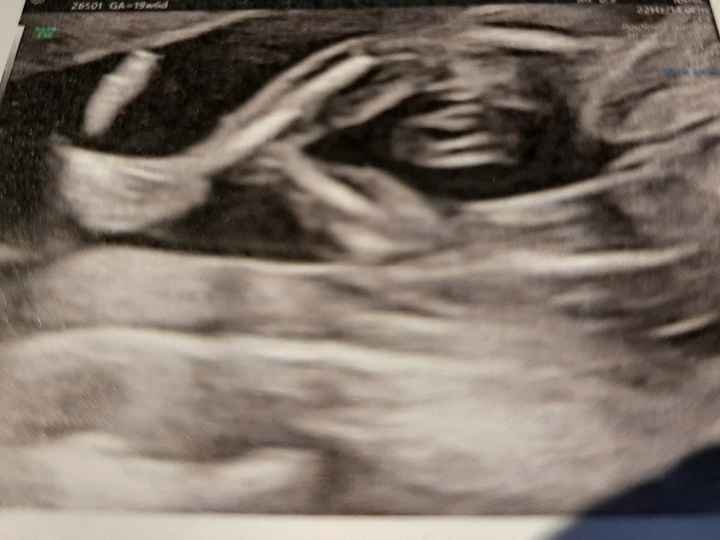

Mancano ancora tantissime settimane alla morfologica, che avrò il 15 Luglio, mi ritrovo spesso a fantasticare se sarà Filippo o Lucrezia, io mi sento maschio ma non si sa mai.

Mi affido a voi esperte di Nub Theory, cosa dite maschio o femmina??